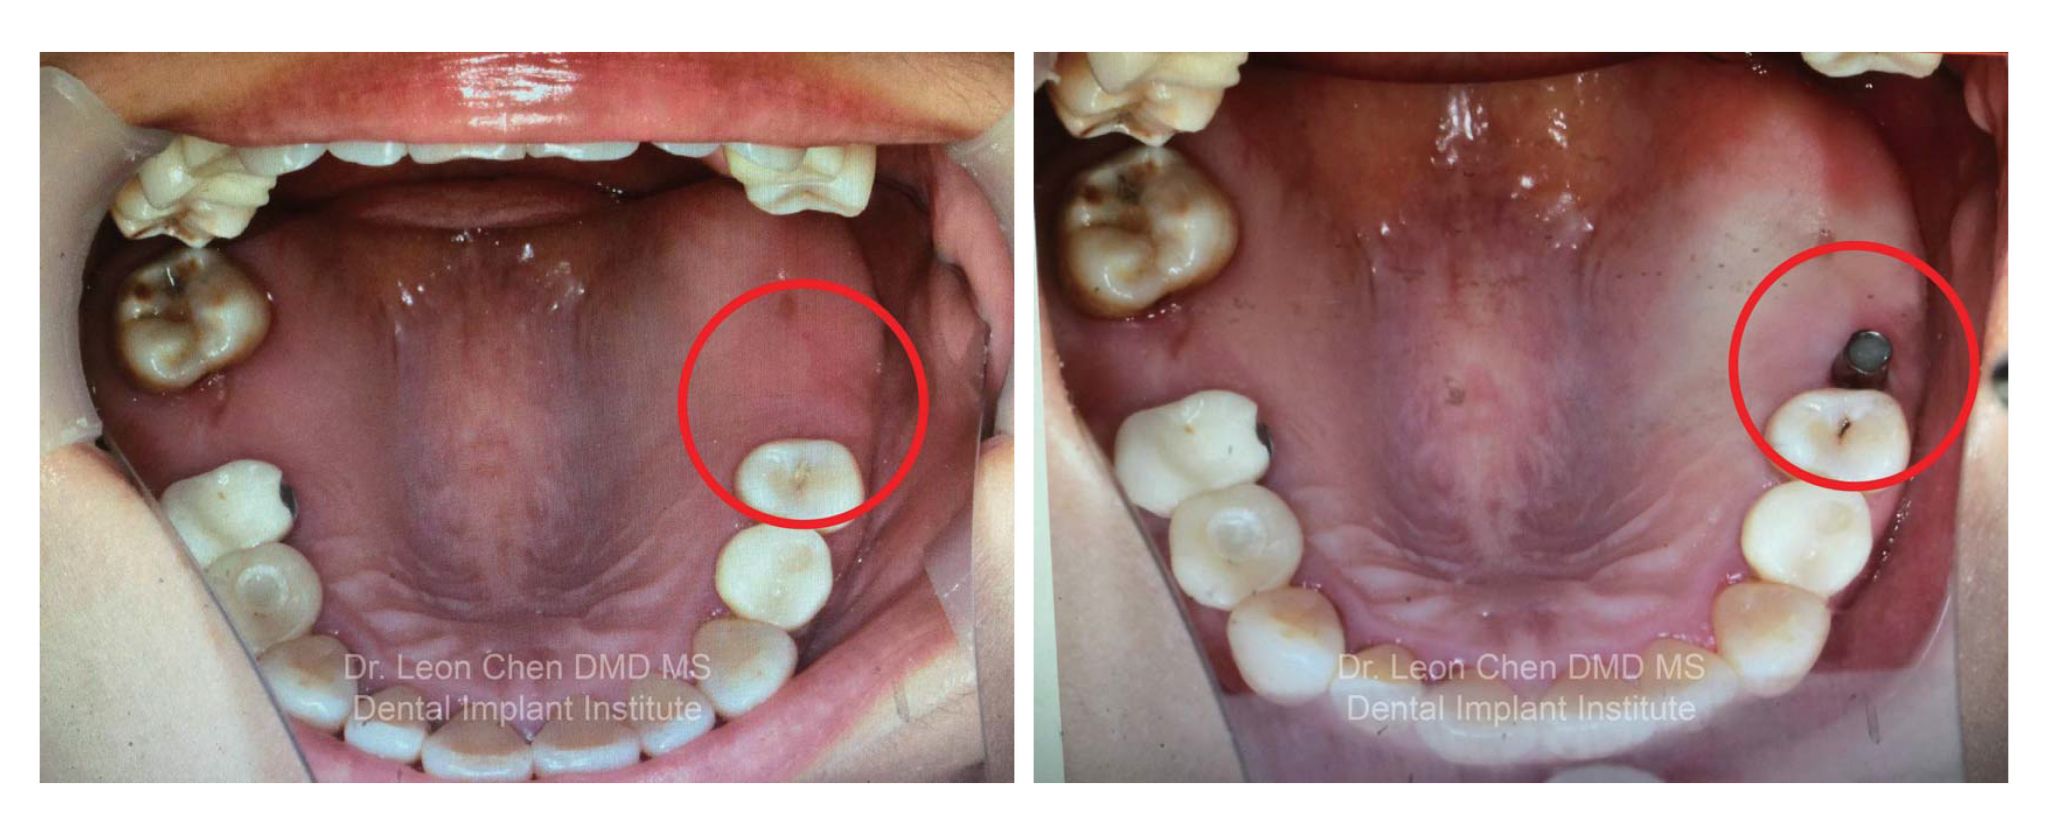

終於到診療那天,細心的陳博士研究我的術前X 光片,向我說明等等要植牙的位置,及所需花費的時間;準備就緒,躺在診療椅上的我,仍有些後悔;貼心的護士捲起一捆一捆的小枕頭,放在我的脖子下方,讓我躺得更舒服些;張開嘴,陳博士一針一針往我的患部周圍打上麻藥,我驚訝地發現:「怎麼不會痛,那地方沒有神經嗎?不對呀!若沒有神經幹嘛打麻藥?還是我昨晚喝太多酒了?也不對呀!原來是真的……他打麻藥一點都不會痛!哇!果真是哈佛名醫。」

耳邊傳來護理人員每隔一段時間報時,應該打了四、五針麻藥吧,陳博士開始植入植體;心裡又暗自擔心,不對呀!要植牙的位置沒有洞,陳博士等等是不是要把牙肉割開挖洞?唉!又是疼痛的過程。為了分散緊張情緒,我心裡默默跟著陳博士的動作數著,哈佛名醫植牙需要多少動作?「 1、2……已經好了?只需要兩個步驟?」

從打麻藥到植一顆牙,前後不到2 分鐘完成!

陳博士分析術前術後的X 光片,我傻傻的看著我的X 光片,除了感動還有感謝。我感動的是陳博士幫我克服對植牙的恐懼,在輕鬆的氛圍下完成植牙手術;感謝的是陳博士讓我不再懼怕看牙醫,而且就如陳博士說的,我另一個臉頰有稍微豐腴……植過牙的臉頰完全不出來有浮腫。